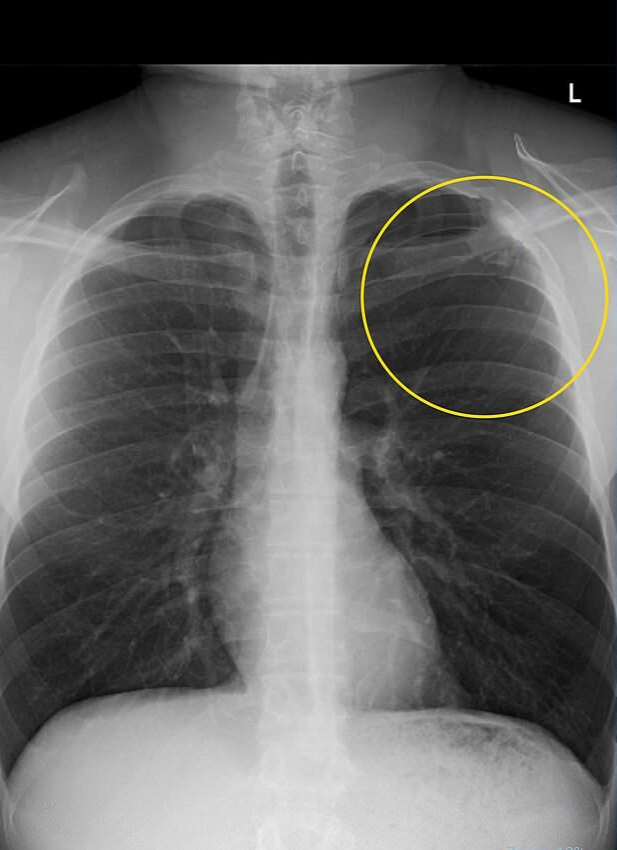

但沉迷于一次性电子烟六年后,这位23岁的年轻人在8月因胃灼热发展成剧烈胸痛而被送医。他说,“大约15分钟内,我就感觉好像有人用霰弹枪击中了我的胸部”。威廉姆斯被紧急送往医院,医生诊断他患有部分肺塌陷,这种情况发生在空气泄漏到胸腔并对肺部施加压力时。

电子烟中数千种可能致癌的化学物质会侵蚀肺组织,导致称为肺大疱的小气囊破裂,进而使肺部塌陷。如果不及时治疗,这可能会导致呼吸困难和胸腔感染。威廉姆斯承认,他曾在网上看到过警告电子烟潜在危险的帖子,包括永久性肺损伤、高血压肺癌,尽管他“从未想过会发生在自己身上”。

威廉姆斯说:“我很幸运,因为有些人会出现全肺塌陷,甚至双肺都塌陷”。“医生说,这百分之百是由吸电子烟引起的,他们还告诉我,即使我不再吸电子烟,这种情况也可能再次发生”。“这太可怕了。我真的很后悔自己吸过电子烟”。

威廉姆斯感到疼痛“从我的肩袖、锁骨、心脏、胸部中央、颈部、耳垂、肺底部到背部”四处蔓延,难以呼吸。在医院,医生告诉他,他的肺部塌陷了10%,这被认为是轻微塌陷。